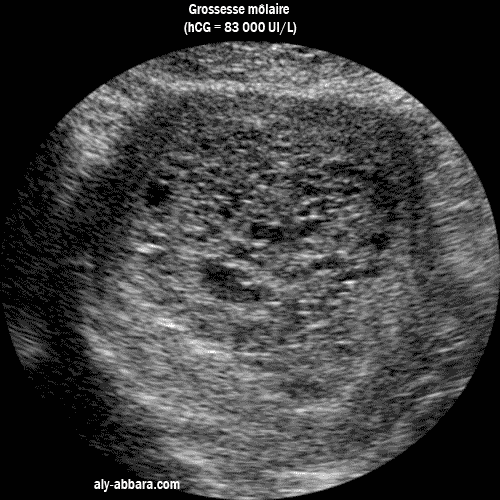

Grossesse môlaire : coupe axiale montrant le contenu utérin.

Image échographique montrant une coupe axiale d'un utérus contenant une grossesse môlaire

avec l'aspect vésiculaire typique de la môle

On remarque bien l'absence de structures embryonnaires ou pré-placentaires reconnaissables